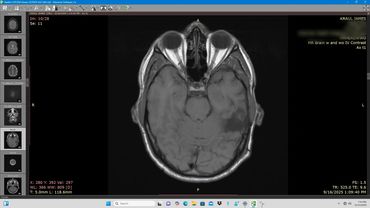

Axial MRI scan showing detailed brain structures including eye sockets and brain tissue.